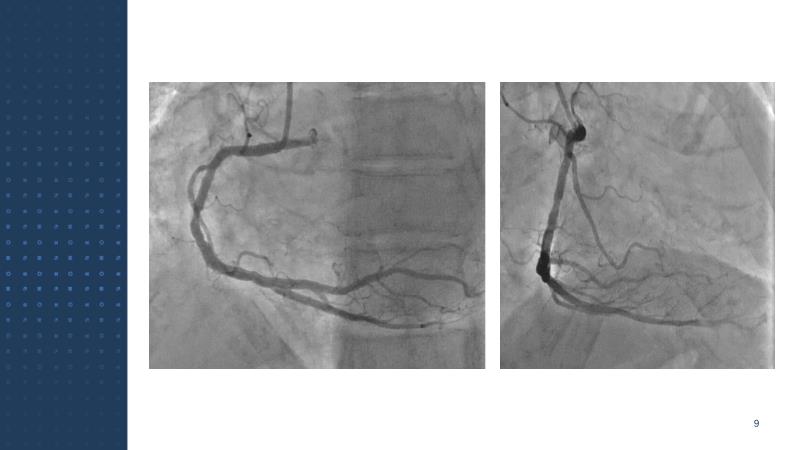

Delve into advanced transcatheter aortic valve implantation (TAVI) with the Evolut FX plus system, focusing on its application in patients with small annulus and coronary artery disease (CAD). This session details step-by-step deployment, patient selection, imaging analysis, and highlights the distinctions from the previous Evolut R platform to improve clinical outcomes.